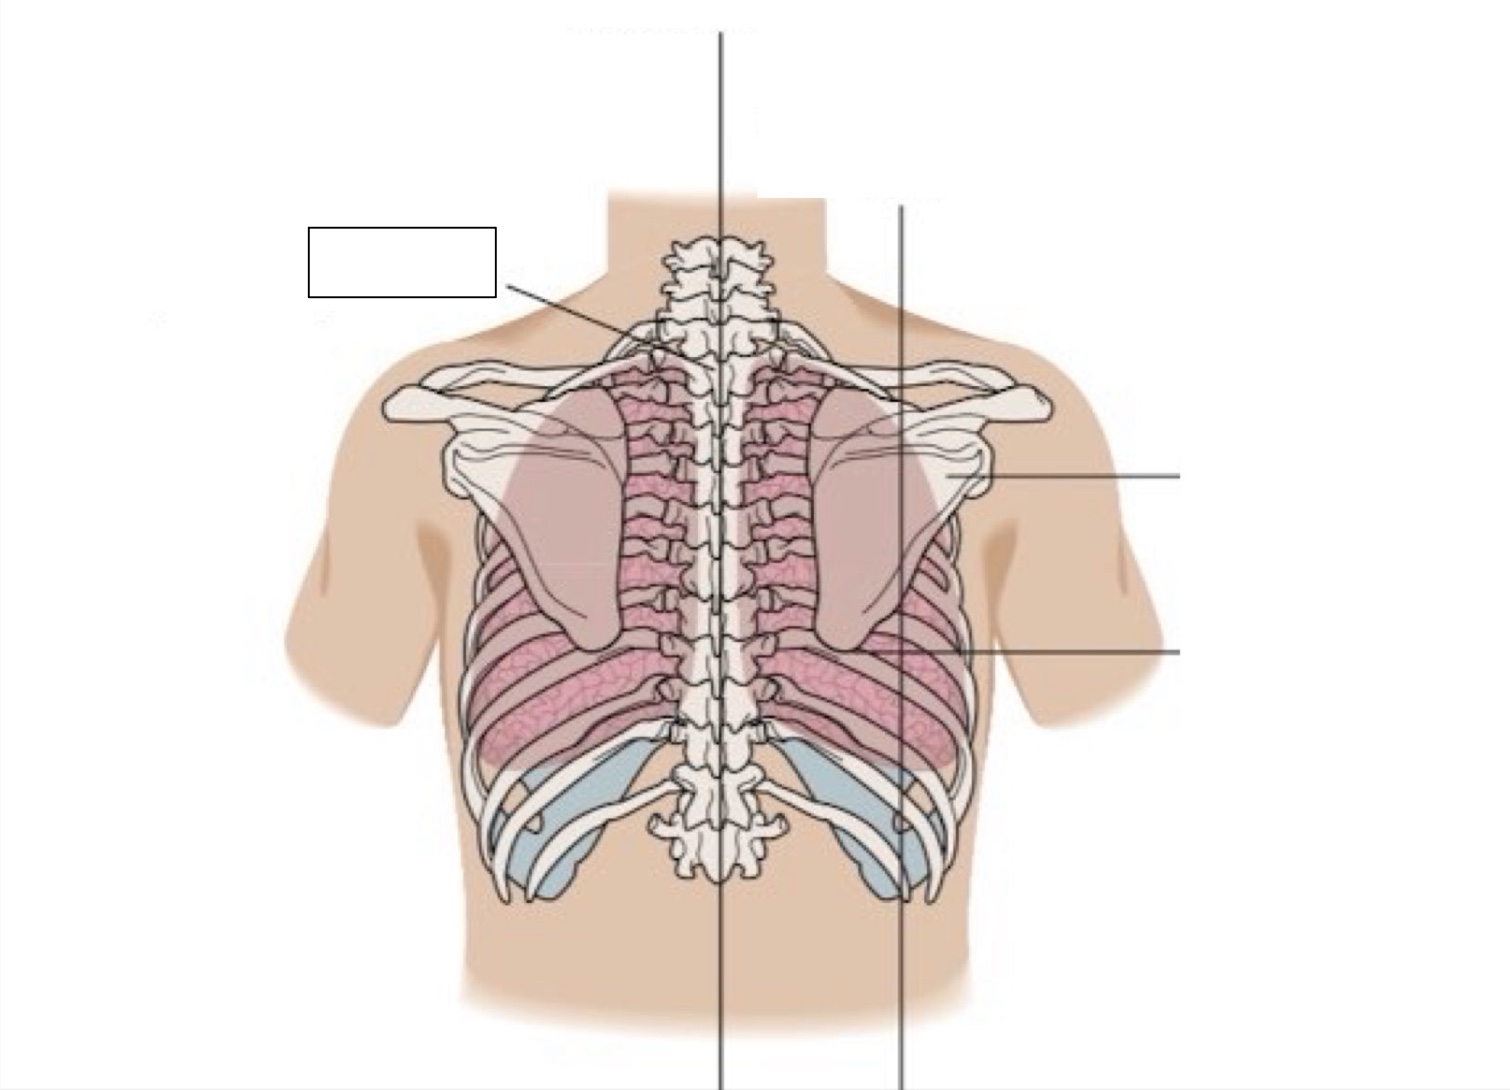

acromion

clavicle

anterior axillary line

midclavicular line

inferior angle of scapula

scapula

midscapular line

midspinal line

spinous process